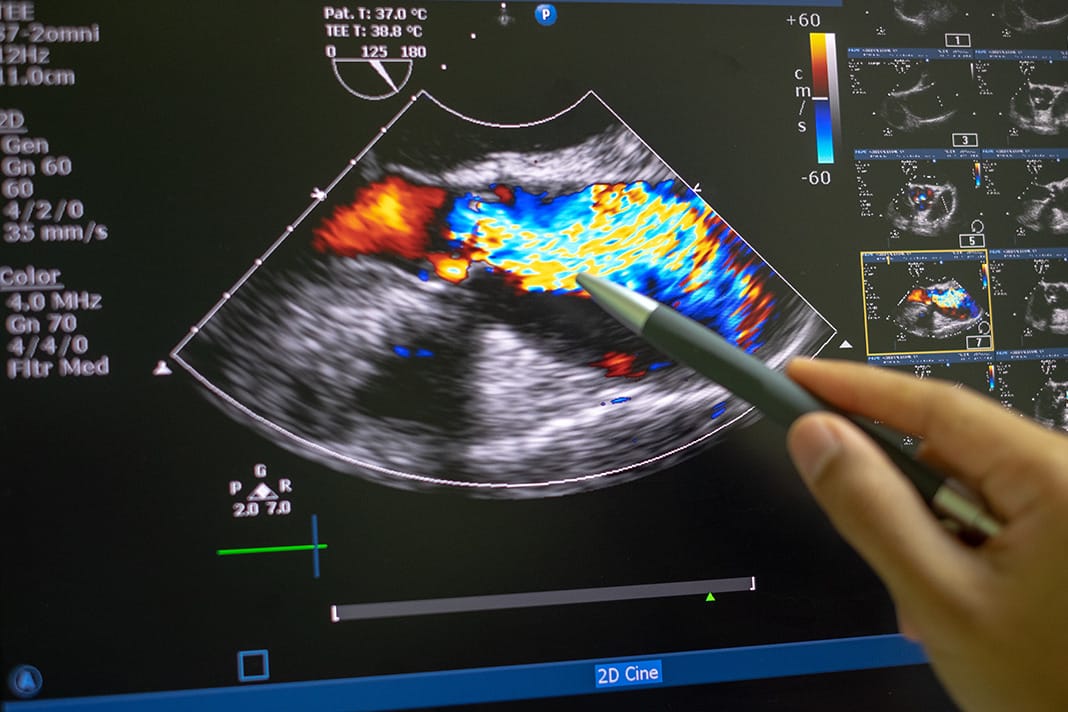

Valvular heart disease (VHD) occurs when a heart valve is damaged and unable to open or close all the way. As a result, the heart has to work harder to circulate blood throughout the body and cause regurgitation, mitral valve prolapse, and stenosis. The first medical condition, regurgitation, can cause a person’s blood to leak back through the valve in the opposite direction, and mitral valve prolapse occurs when the valve doesn’t close all the way. Stenosis occurs when the heart valve can’t open, and the blood can’t flow through it. If left untreated, valvular heart disease can lead to sudden cardiac arrest, heart failure, and possibly death.